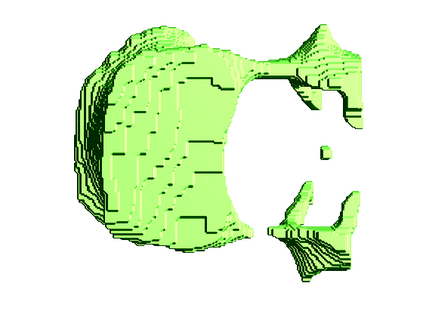

In this paper we present a new 3D segmentation approach for the vertebrae of the lower thoracic and the lumbar spine in spiral computed tomography datasets. We implemented a multi-step procedure. Its main components are deformable models, volume growing, and morphological operations. The performance analysis that included an evaluation of accuracy using the European Spine Phantom, and of intra-operator precision using clinical CT datasets from 10 patients highlight the potential for clinical use. The intra-operator precision of the segmentation procedure was better than 1% for Bone Mineral Density (BMD) and better than 1.8% for volume. The long-term goal of this work is to enable better fracture prediction and improved patient monitoring in the field of osteoporosis. A true 3D segmentation also enables an accurate measurement of geometrical parameters that can augment the classical measurement of BMD.